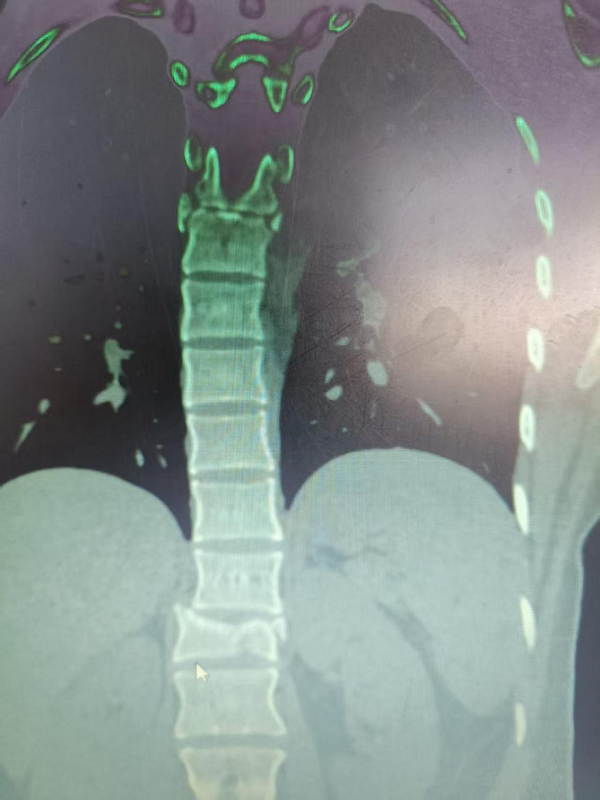

在丁晔副主任医师带领下,团队联合彭晴医师等医护人员,成功完成3台分属颈、胸、腰椎三大区域的高难度脊柱外科手术,病种涵盖退行性病变与创伤性骨折,融合微创内镜与经典开放技术,彰显科室综合诊疗实力。

3. 为胸椎爆裂性骨折患者施后路切开复位、微创减压内固定术(四级手术),胸椎爆裂性骨折常因高能量损伤导致,骨折块可能突入椎管压迫脊髓,致残风险高。丁晔副主任医师团队采用微创理念进行减压,并完成了有效的复位与坚强的内固定,既解除了对神经的压迫,又最大程度地减少了手术创伤,为患者争取了最佳的神经功能恢复条件。

三台手术均顺利完成,患者术后恢复良好,标志着我院脊柱疾病微创化、精准化治疗迈上新台阶。